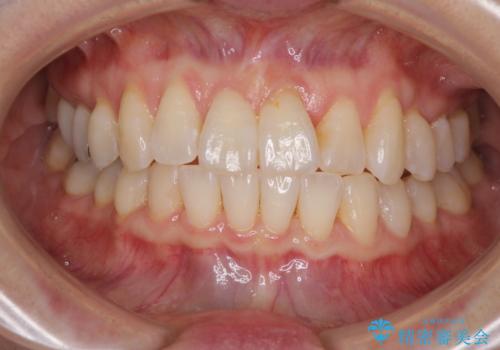

前歯のクロスバイト インビザライン矯正で改善

- むし歯治療を契機に、長年気にしていた前歯のクロスバイトの改善を希望された患者様です。

汚れが溜まりやすく、歯ぎしりがうまくできないため、インビザラインを用いて矯正治療を行うこととしました。

インビザラインによる前歯のクロスバイトの改善は、治療期間中に前歯でしか咬めない時期が続いたり、歯肉退縮や歯髄壊死のリスクが高まったりと、治療中にトラブルを抱えることがあります。

特に上顎側切歯(真ん中から2番目の歯)が舌側に引っ込んでいるケースは、インビザラインでは改善しきれないことがあると言われています。